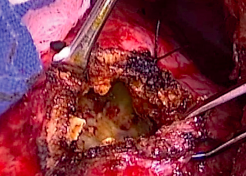

Resultados: Paciente con diagnóstico de quiste hidatídico en tránsito hepatotorácico con fistula biliobronquial fue sometida a toracotomía con cuña de pulmón, seccionando remanente en comunicación con quiste. Paciente presenta evolución clínica e imagenológica favorable.

Conclusión: Tratamiento quirúrgico dependerá de localización de la lesión, estado del quiste, tamaño y experiencia del equipo quirúrgico, siendo una quistoperiquistectomía con tratamiento de los trayectos fistulosos una buena alternativa.